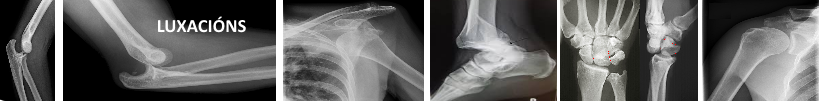

- Luxación, saída dun óso da súa posición na articulación a causa dun movemento brusco ou golpe violento. O óso desprázase a nunha posición anormal polo que se observa unha deformidade na zona afectada.

Coñecemos varios tipos de luxacións segundo a zona ou o lugar onde se dan.Así falamos de luxación de cadeira, ombreiro, cóbado, dedos e dedas, boneca, xeonllo...